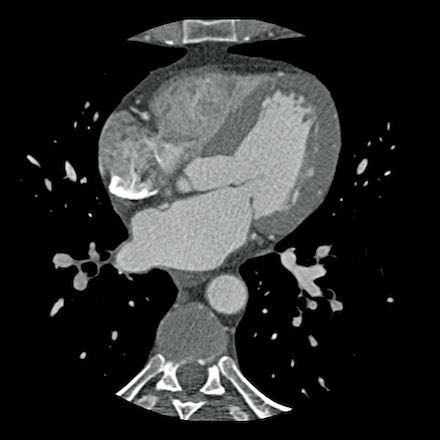

Same patient. First, study the CTA image.

How would you describe the findings?

The coronal image shows a central low-attenuation area around the lumen

of the LAD.

This low-attenuation area is surrounded by a higher attenuation

area.

This finding is the earlier discussed napkin-ring sign, which is a high-risk

plaque feature.

This patient classifies as CAD-RADS 4A/P1/HRP.